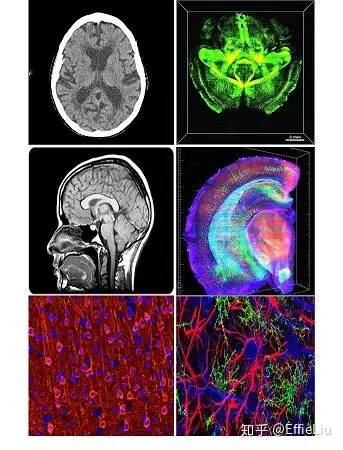

与常见的黑白CT, MRI图,以及稍微有那么一点颜色的免疫组化图相比,这些色彩鲜艳的3D高清大图肯定让你眼前一亮吧!他们怎样拍出完整大脑的三维视频呢?接下来我们就来一步步揭开它的炫彩面纱!

左:“低配版”图;右:“高配版”